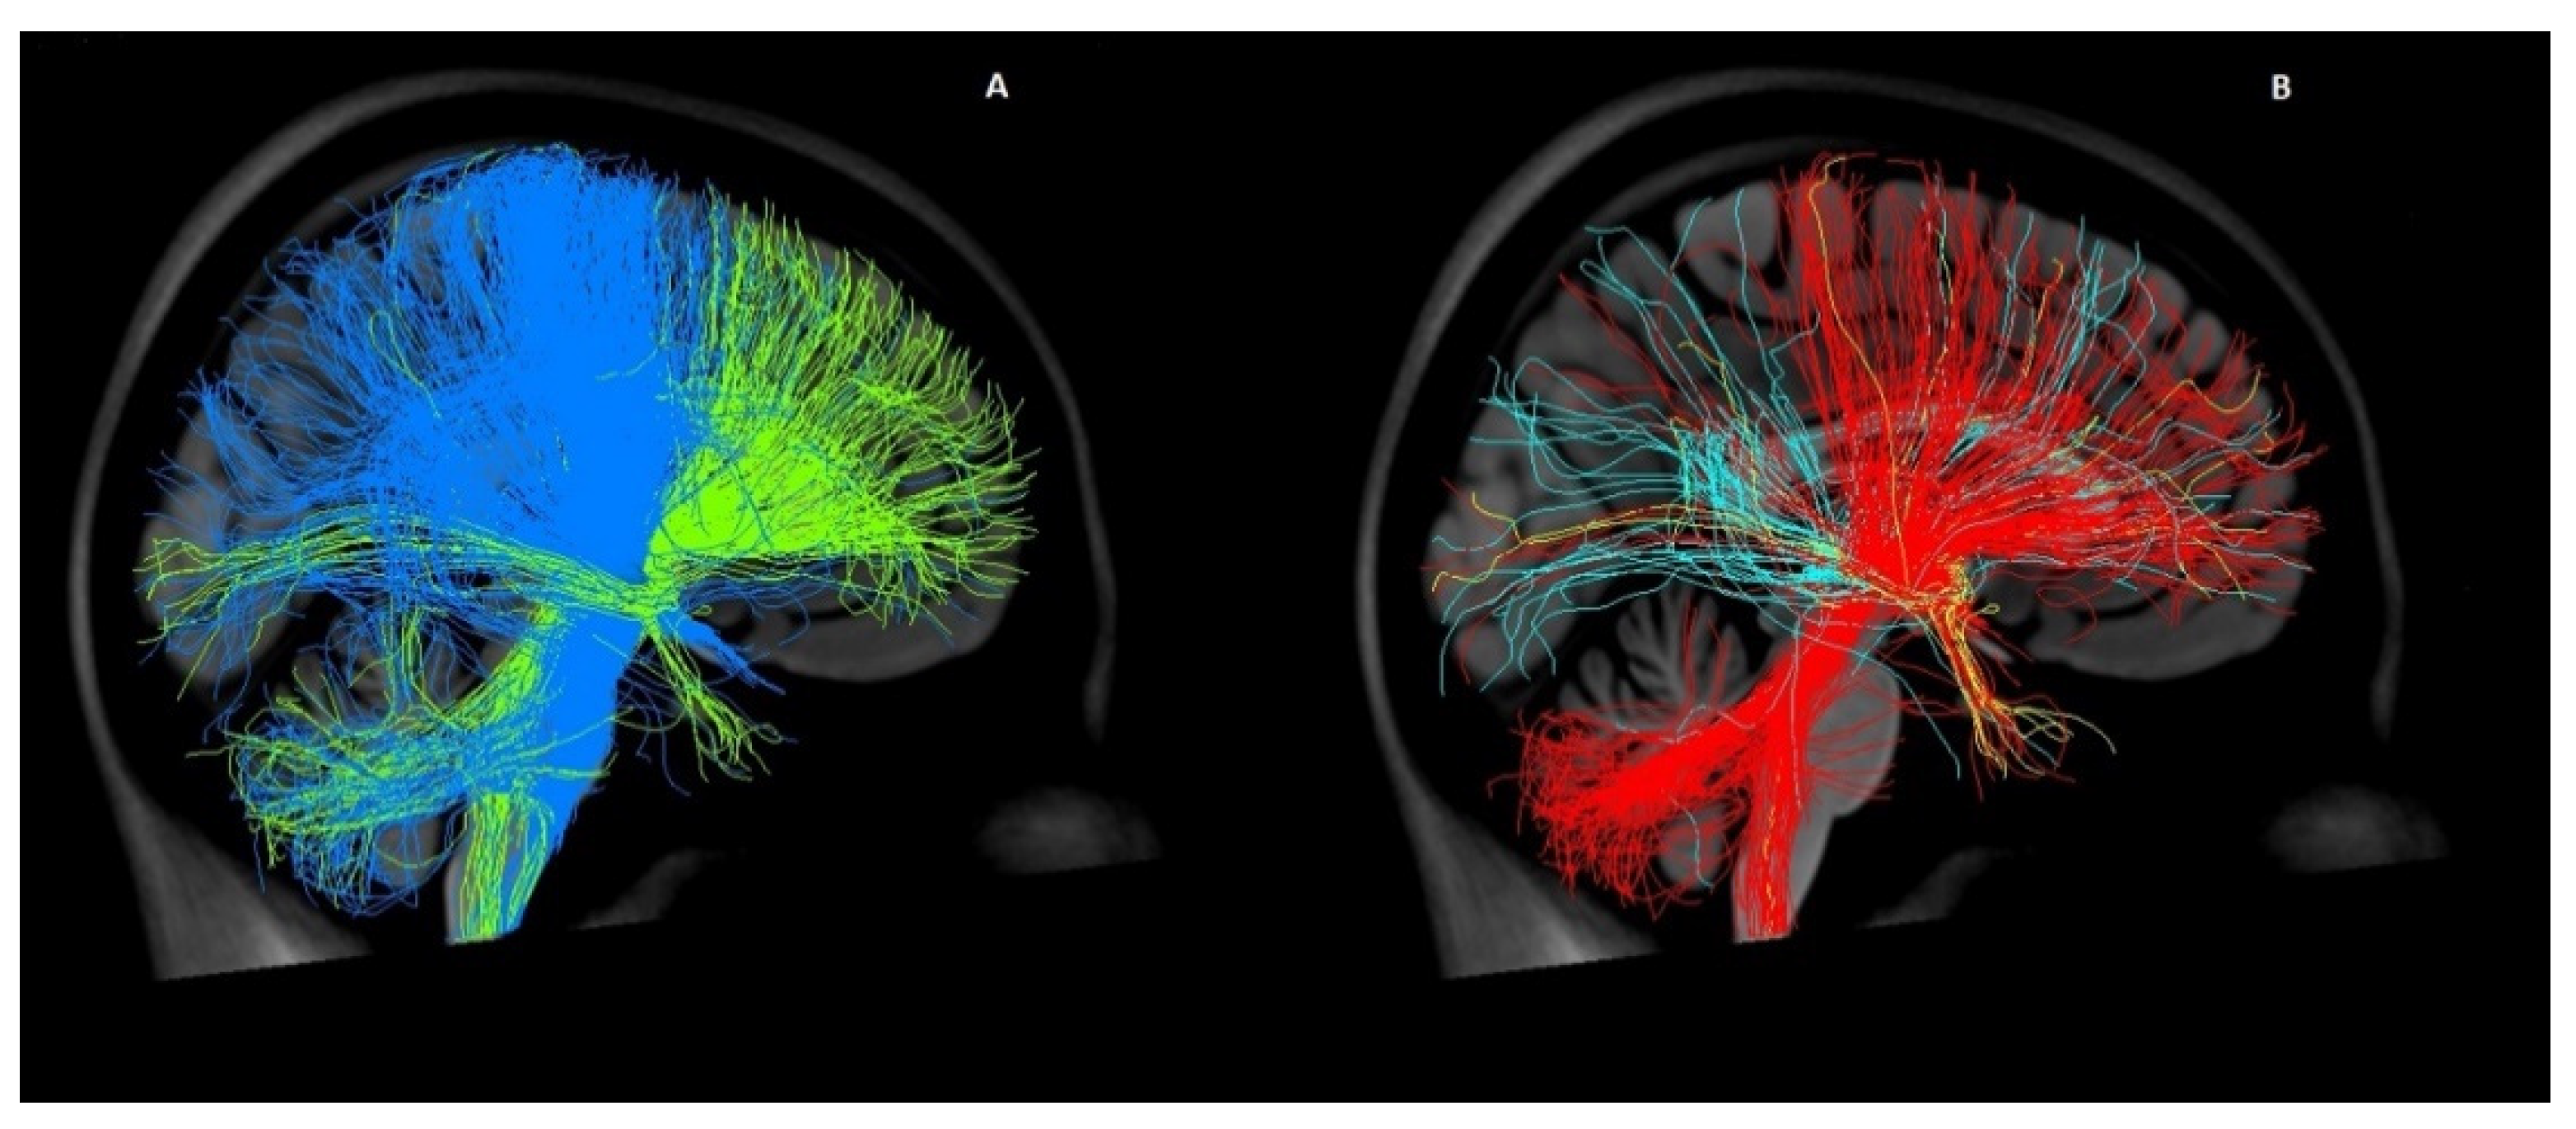

Our analysis showed significant differences within the pallidal and also within the thalamic targets (Figure 5). In previous tractography studies, the CM-Pf and the CM/Voi were merged into one target, and in some cases the two pallidal targets were also regarded as one [,]. Based on our findings, all targets must be analyzed separately to provide a recommendation for lead placement or targeted stimulation.

Figure 5.

Comparison of the connectivity profiles of different DBS targets in GTS. Both figures show fiber tracts from the selected targets connecting to the entire brain in a three-dimensional lateral view from the left in the MNI space using a normative connectome. (A) displays tracts from the posteroventral globus pallidus internus (pvGPi) in blue and tracts from the anteromedial globus pallidus internus (amGPI) in green. In (B), the tracts from the ventral anterior/ventrolateral thalamus (VA/VL) are represented in red, the tracts from the centromedian nucleus/parafascicular (CM-Pf) in light blue, and the tracts from the CM/ventro-oralis internus (CM/Voi) in yellow.